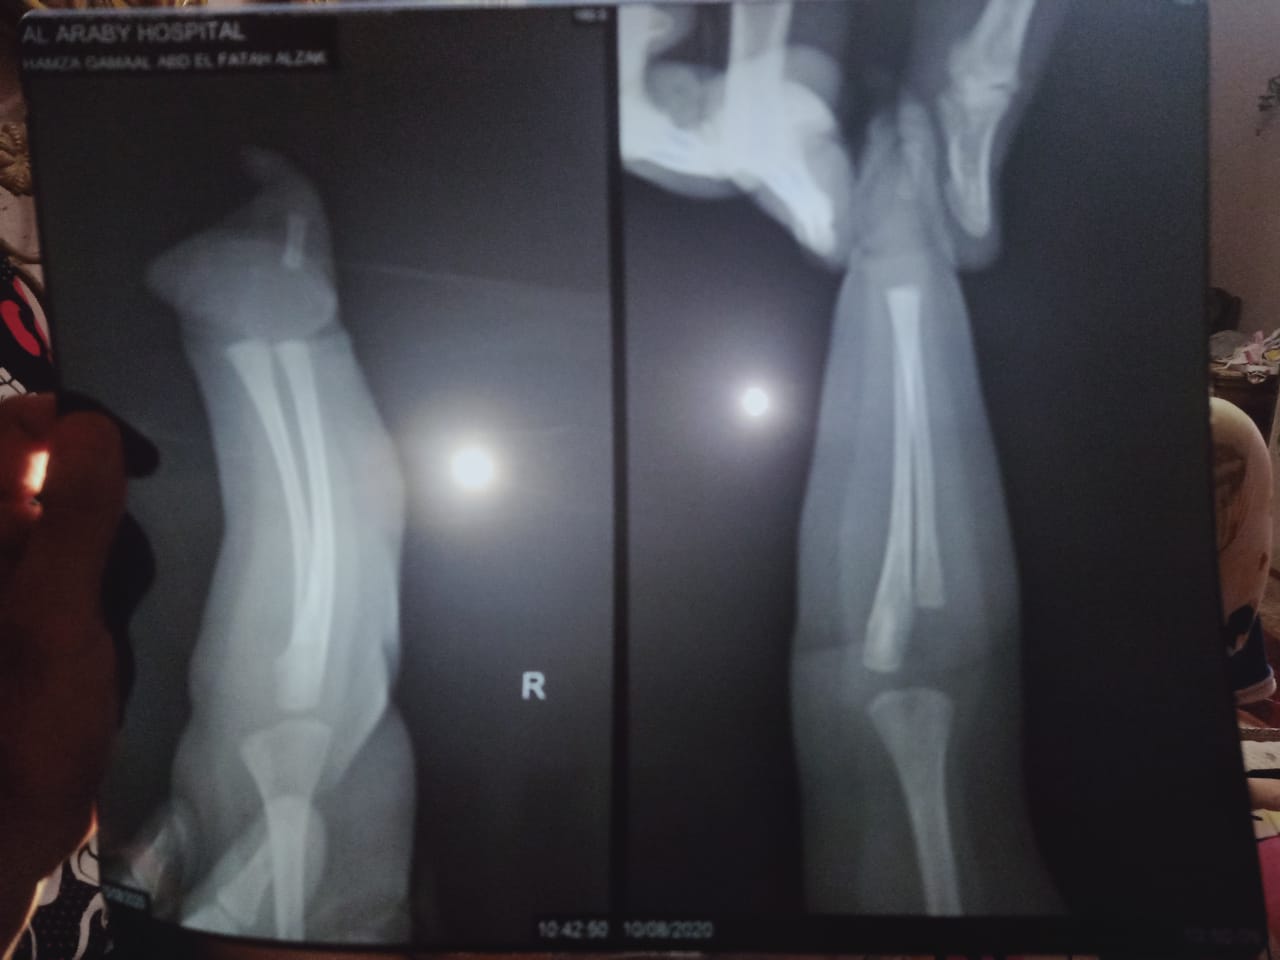

"وُلد بأصبع واحد فقط".. أم تستغيث لعلاج طفلها (صور)

الطفل حمزة

تستغيث السيدة نسمة محمد، لعلاج طفلها ذوو الـ8 أشهر فقط، الذي ولد بحادثة نادرة من نوعها، وهي ولدته دون كف مع وجود أصبع واحد فقط في يديه اليمني.

وقالت "للقاهرة 24"، حمزة من ساعة ما اتولد وهو كده، دلوقتي عنده 8 أشهر، معندوش كف ولا أصابع في ايديه اليمين، غير أصبع واحد بس وعضلة الكتف كمان مش موجودة، مشيرة:" محدش عارف أيه سببه".

وأضافت:" أنها ذهبت إلى العديد من الأطباء لمعرفة أسباب وعلاج طفلها، إلا أن الأراء انقسمت حول أن المرض ليس له علاج، أو إجراء عملية جراحية كبرى للطفل وأخذ عظام من الساق.